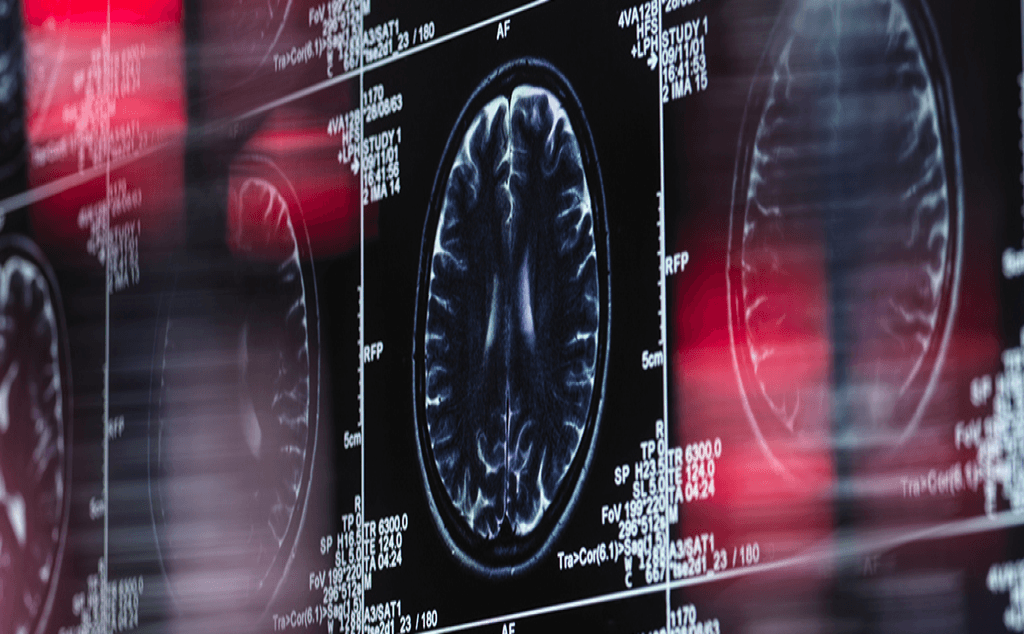

Estos resultados contradictorios podrían sugerir mecanismos únicos entre los pacientes con el tipo de dolor de espalda que conduce a una prescripción de gabapentina que también aumenta su riesgo de demencia, como un cierto tipo de ubicación de la inflamación. Pero la gabapentina actúa inhibiendo algunos de los canales de comunicación clave del cerebro para aliviar el dolor o reducir la probabilidad de convulsiones. Por lo tanto, la preocupación es que también podría dañar las conexiones entre neuronas, lo que podría provocar demencia, una preocupación respaldada por este último estudio. La demencia es una enfermedad difícil de estudiar, con muchos factores potenciales a tener en cuenta, pero cada estudio nos acerca al panorama completo de cómo se deteriora el cerebro con el tiempo.